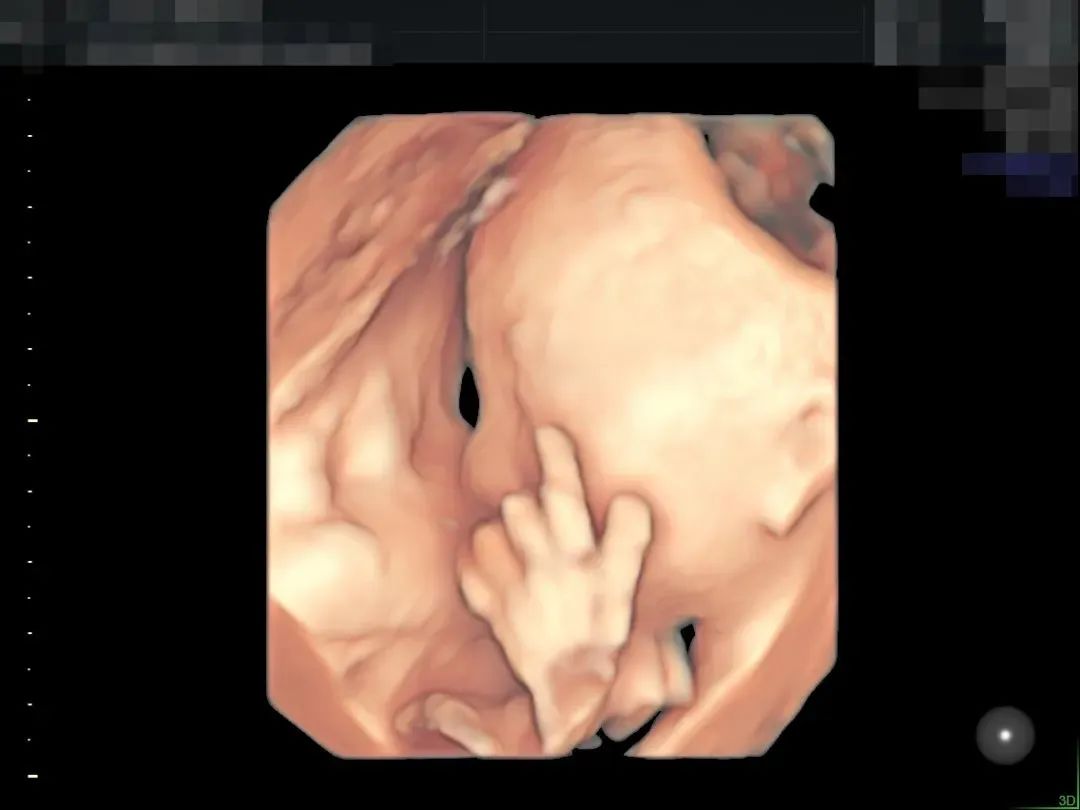

▲孕妈肚皮脂肪较厚,羊水情况也不好,在和平进行了全面筛查

超高清画质立体显示胎儿面部、脏器、四肢脊柱等发育情况,可高效筛查胎儿唇裂、骨骼发育异常以及中枢神经系统、呼吸系统、消化系统、泌尿系统、心脏的重大畸形。金标E10具备一整套胎心成像技术,支持从胎儿心脏结构到心功能的分析,可真实呈现胎心结构、脐带、血流变化,帮助临床医生及时作出诊断。“金标版”E10超真动态显示胎儿实时活动图像,画质全面颠覆传统视觉理念,堪比IMAX电影大片,让您看得更清晰、更直观。“金标版”GE-E10四维彩超,采用人体工程学设计,不存在射线、光波和电磁波等方面的辐射,对人体健康没有影响,孕妈妈们也可以安心检查。